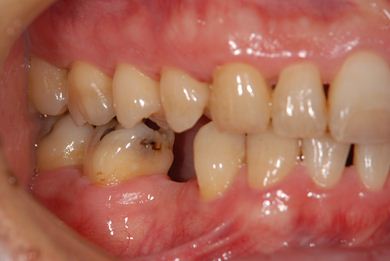

| 性別/年齢 | 男性 / 37歳 | ||||||||||||||||||||||||||||||||

| 主訴 | 前歯(2本)の欠けの治療 | ||||||||||||||||||||||||||||||||

| 治療方針 | 右下欠損部分をインプラント治療にて、機能的・審美的回復を行う。 | ||||||||||||||||||||||||||||||||

| 治療内容 | インプラント1本、メタルボンドセラミッククラウン1本 | ||||||||||||||||||||||||||||||||

| 総治療費 | 252,000円 | ||||||||||||||||||||||||||||||||

| 治療期間 | 7ヶ月 |